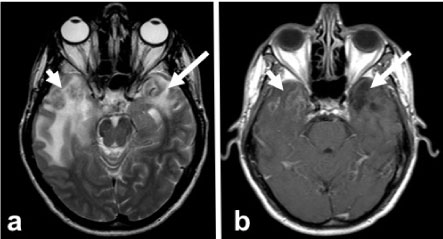

Figure 3: 18 months control MRI. Axial T2A (a) and T1A (b) images show the disappearance of edema and mass in both temporal lobes and encephalomalacia and gliosis (arrows). View Figure 3